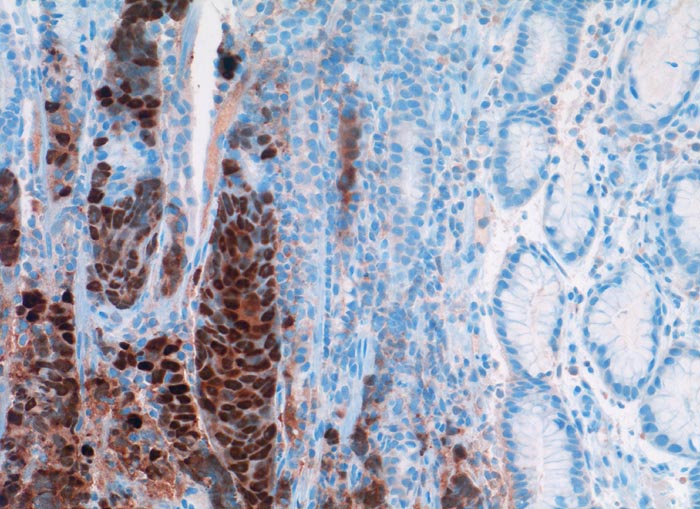

Metastase: invasiv duktales Mammakarzinom

Magenantrum

Die Tumorzellen füllen die Drüsenschläuche des Magens aus und verdrängen die orstständigen Zellen. Die Tumorzellkerne sind stark positiv für den Östrogenrezeptor.

Seit 21 Monaten bekannte Metastasen eines invasiv duktalen Mammakarzinoms im Magenantrum

Immunhistochemie

Oestrogen Rezeptor

200